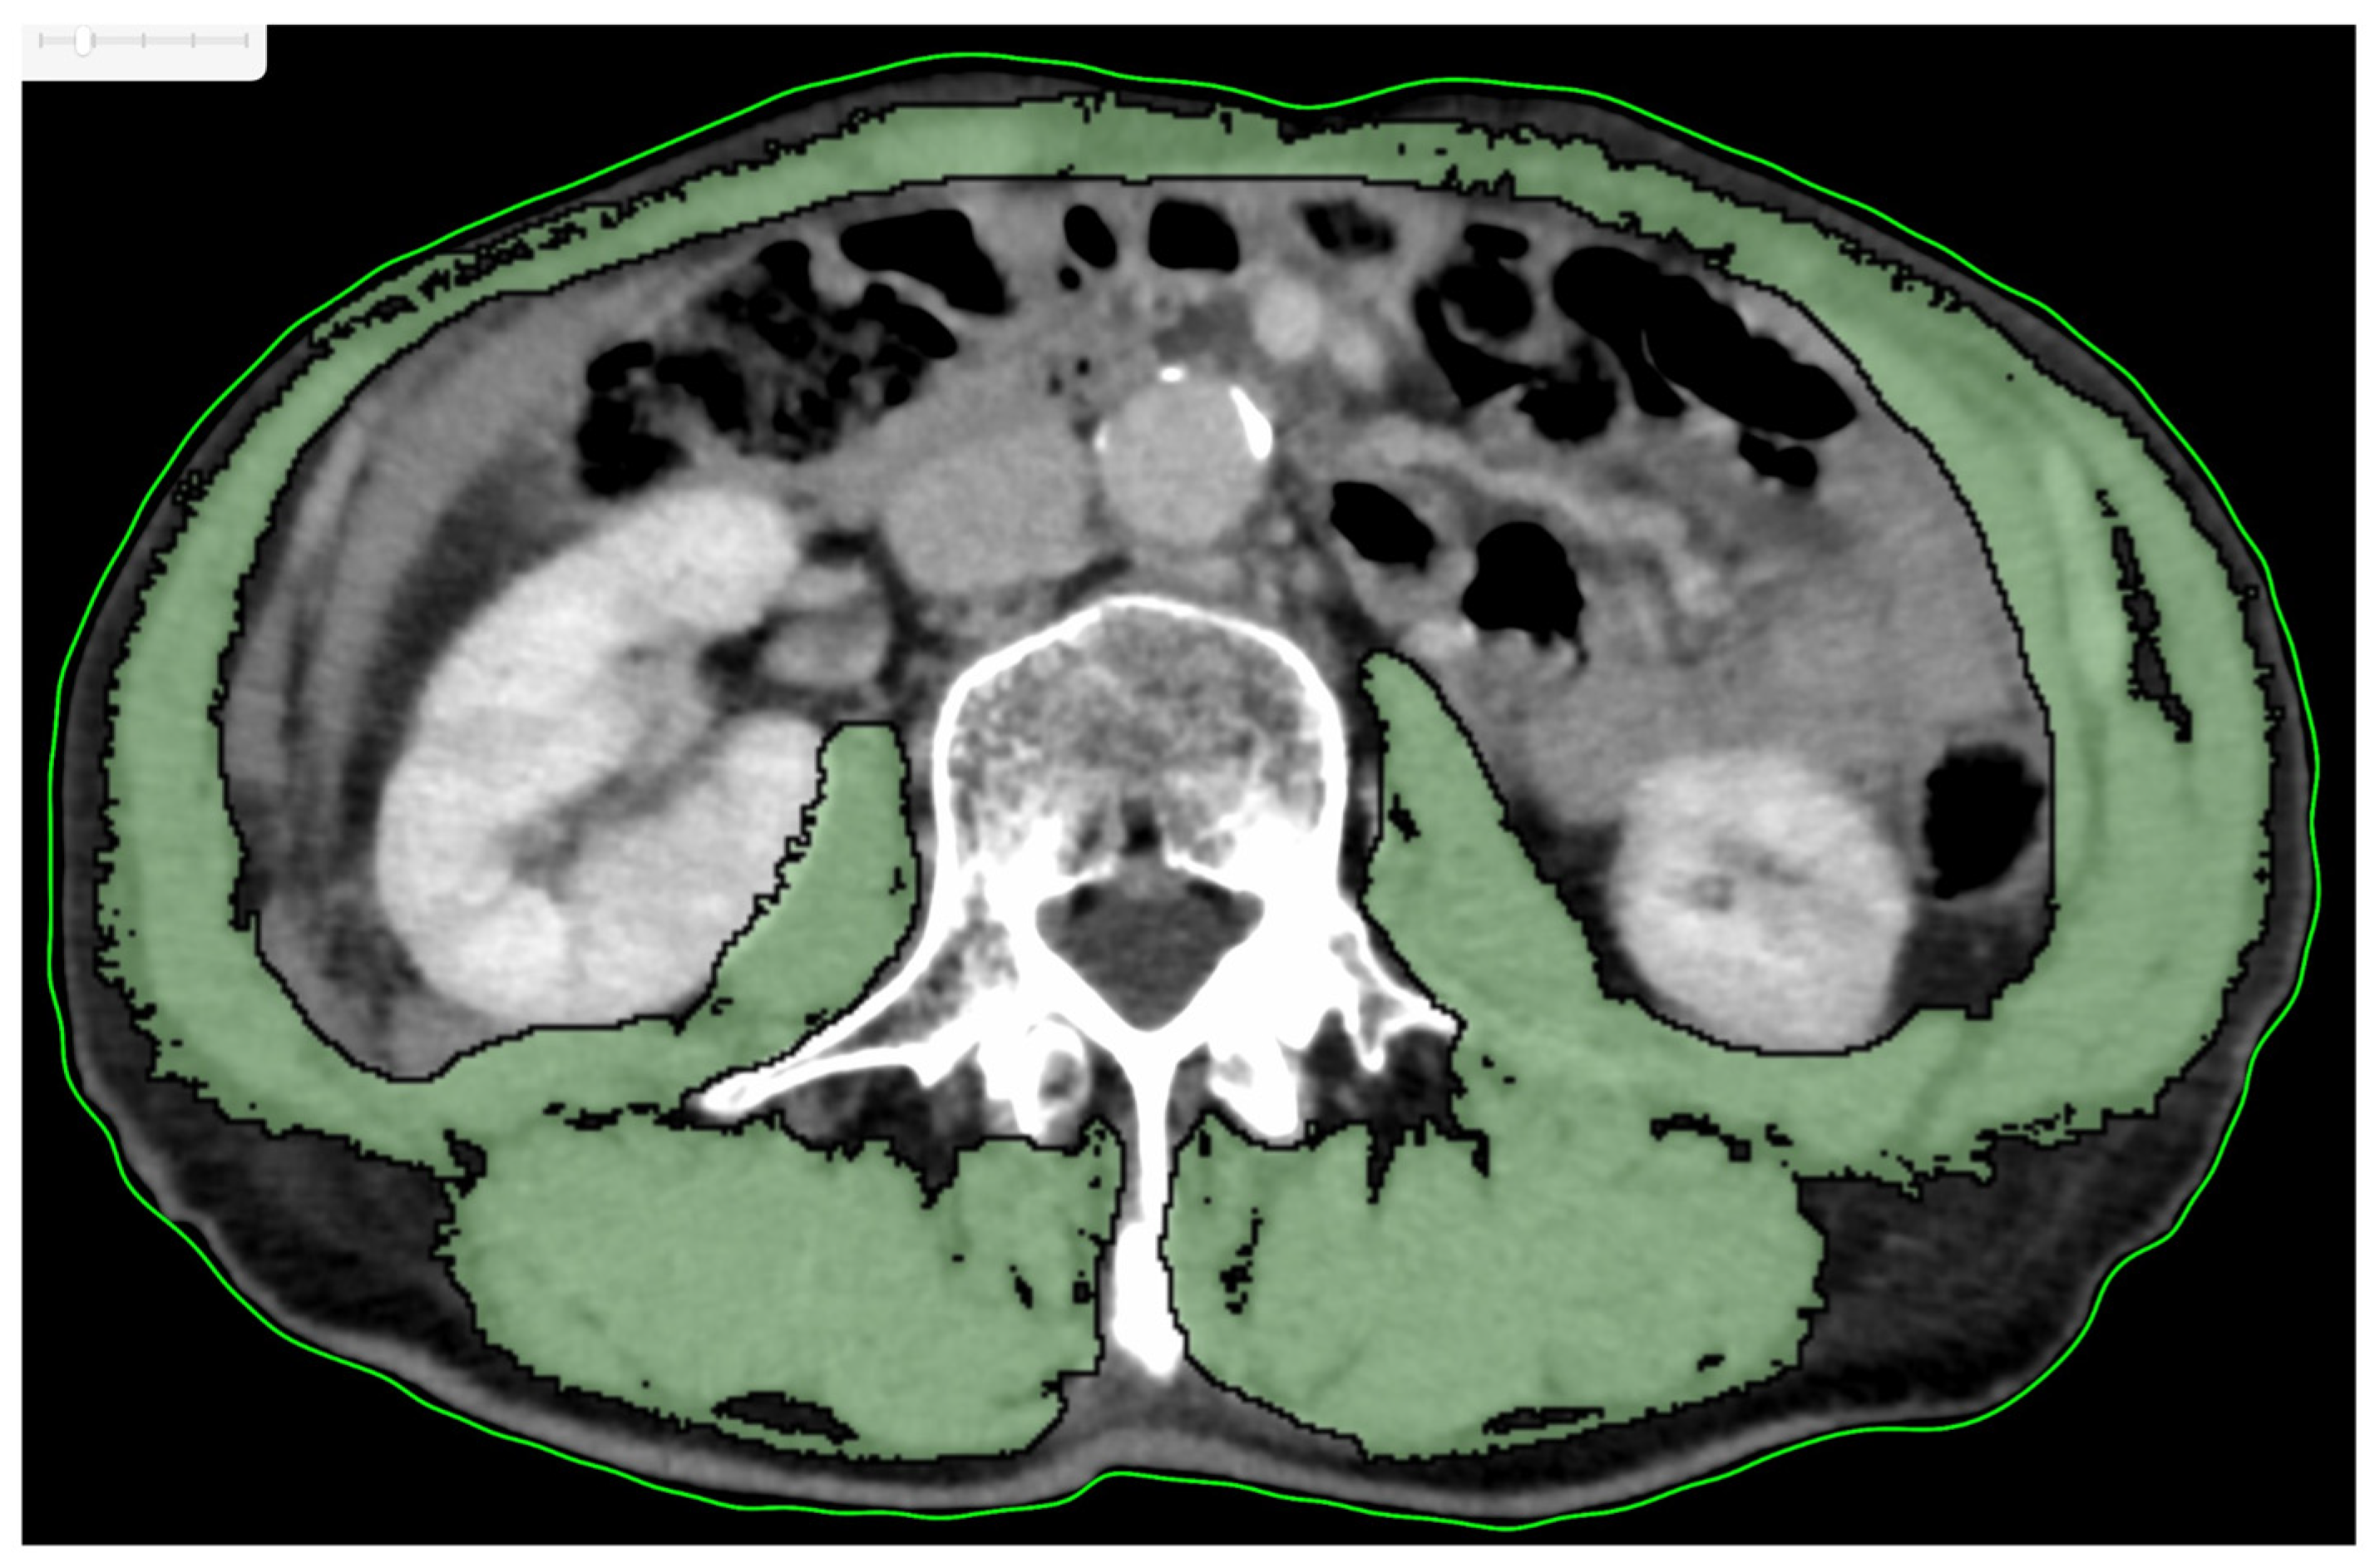

2.2. Study Variables